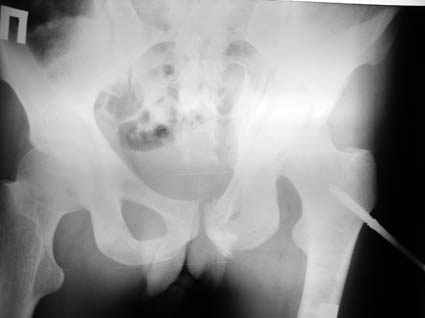

Это обзорные и косые снимки